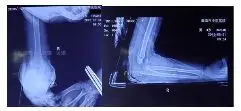

外院拍片情况如下:

GartlandⅢ型肱骨髁上骨折患者,患肢畸形、肿胀明显。肘前方可见皱褶,典型的难复型肱骨髁上骨折。